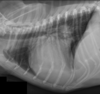

Q

Which structures are outlined in this image?

A

dark blue: left atrium

pink: left ventricle

yellow arrow: sulcus at the junction of left atrium and left ventricle

How well did you know this?